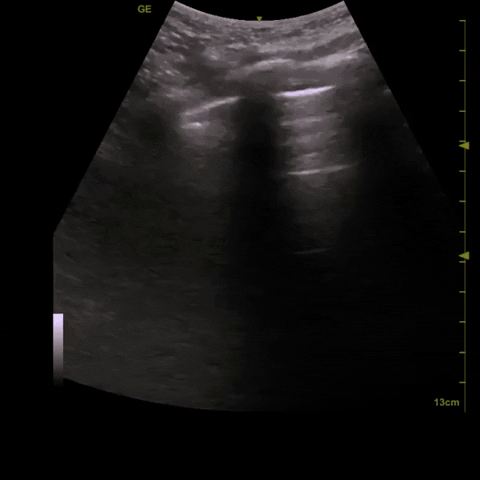

Here are clips from the initial lung POCUS: